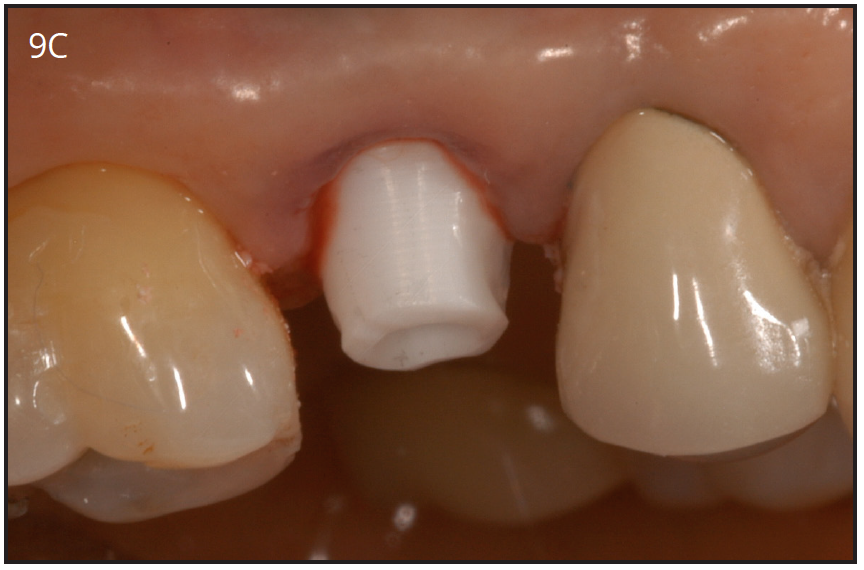

The implant platform can also have different shapes. It can be internal connection or external connection with the abutment. The original Branemak system had an external connection. The internal connection platform is the most preferred today in dental practices due to ease of handling. (Figures 9A-C)

Figure 9A – Internal connection implant system – implant placed

post-extraction

Figure 9A

Figure 9B – Prefabricated zirconia abutment fitting the internal connection in Figure 9A

Figure 9B

Figure 9C – Zirconia abutment torque onto implant

Figure 9C